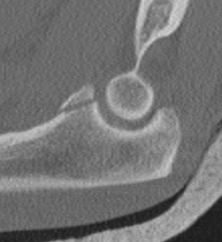

Regan and Morrey classification of transverse coronoid fractures

Elbow stability related to size of coronoid fragment

| Type I | Type II | Type III |

|---|---|---|

| Small coronoid process fracture | 50% of coronoid process | > 50% coronoid process |

| Usually stable |

Capsular attachment Elbw may be unstable |

Capsule + MCL attachment Elbow unstable

|